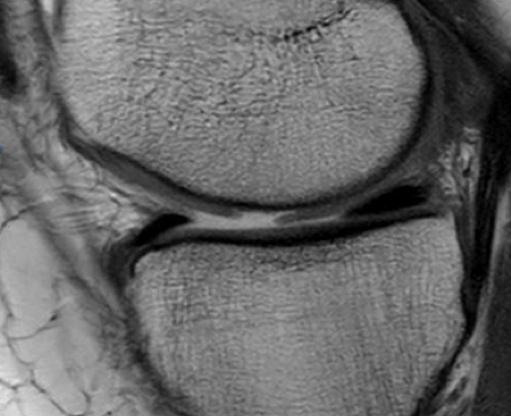

There are several surgical options described for osteochondral defects of the knee. The aim of our study was to analyze a series of patients treated with mosaicplasty with an average of 8 years follow-up.            Sixty-two patients with osteochondral defects of the knee who underwent mosaicplasties between 2001 and 2014 were included in the study with minimum follow-up of 2 years. Patients were evaluated using the Lysholm score, International Knee Documentation Committee Score (IKDC) and Kellgren-Lawrence radiographic scale.            Forty-five were men and seventeen women with an average age of 36 years old. Mosaicplasties were 45 in the medial condyle, 12 lateral condyle, 12 trochlea and 3 combined. Forty-two patients had isolated mosaicplasties and 20 patients presented associated surgical procedures (osteotomy, ACL reconstruction, meniscectomy). The mean results of the Lysholm score were 80.1 and IKDC was 66.7. There were no significant differences among the Lysholm and IKDC scores between these two groups. In 30 patients evaluated with radiography a satisfactory inclusion of the bony block was observed.            We believe that mosaicplasty is a procedure with a high degree of satisfaction with good functional results in patients with focal lesions of articular cartilage that may or may not be associated to other surgical procedures.